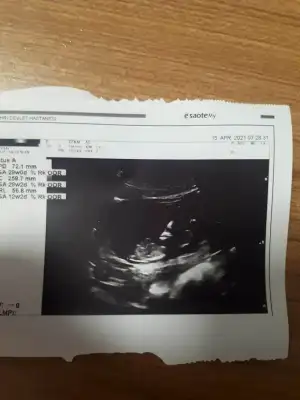

Rica etsem usg mize bakabilir misinizEmin olamadımkız olabilir

Erkek sanki11+5 haftalık rica etsem bana da tahminde bulunur musun ?

Erkek sanki

benimkini de yorumlar misiniz 11 haftalikErkek sanki

Erkek sanki emin olamadım başka USG varsa paylaşın